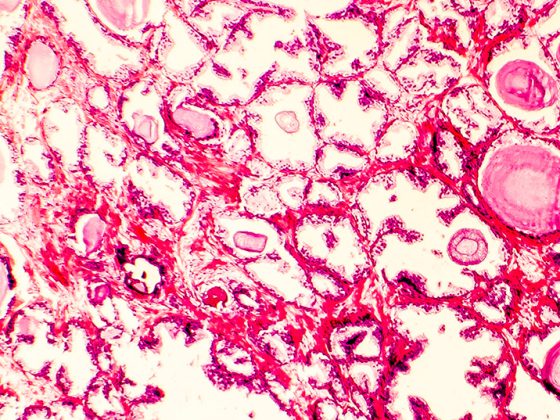

Eine geringe körperliche Leistungsfähigkeit und Muskelkraft im frühen Erwachsenenalter sind Risikofaktoren für kardiovaskuläre Erkrankungen (CVD). Es ist jedoch unklar, wie diese Faktoren mit subklinischer Atherosklerose zusammenhängen, da es an Längsschnittstudien mangelt. In einer kürzlich veröffentlichten Studie wurde nun untersucht, ob die körperliche Leistungs­fähigkeit und Muskelkraft im frühen Erwachsenenalter mit der subklinischen Atherosklerose im späteren Erwachsenenalter zusammenhängen.